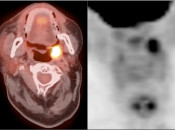

Palatine Tonsils

The palatine tonsils frequently demonstrate very intense metabolic activity.

Interpretation of tonsillar uptake is depends on the clinical presentation of the patient, the degree of FDG uptake, the size of the tonsils and the bilateral or unilateral nature of the findings.

- Bilateral and fairly symmetric FDG-uptake in non-enlarged palatine tonsils is almost always a normal finding.

- Bilateral and fairly symmetric FDG-uptake in enlarged palatine tonsils is nearly always inflammatory in nature (although can occasionally be seen with lymphoma).

- Unilateral or asymmetric increased FDG uptake within one palatine tonsil warrants careful and detailed assessment (addressed in detail, here).